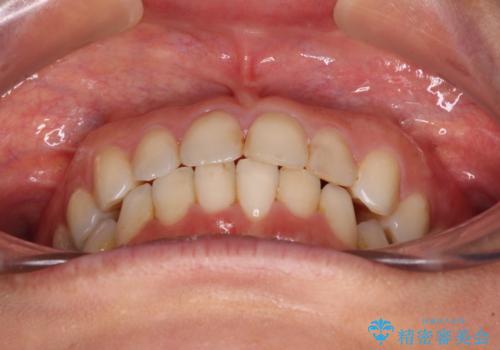

- 前歯のデコボコを気にして来院された患者様です。

IPR(歯と歯の間を削る)によってデコボコが解消するように設計し、インビザラインにより治療を行うこととしました。

下顎善の叢生をもう少し改善したかったのですが、患者様は十分に整ったとのことで治療を終えることになりました。